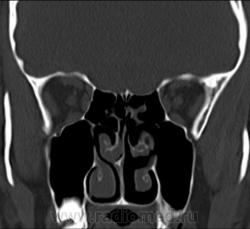

1. Эктопия зуба?

2. Хронический гайморит?